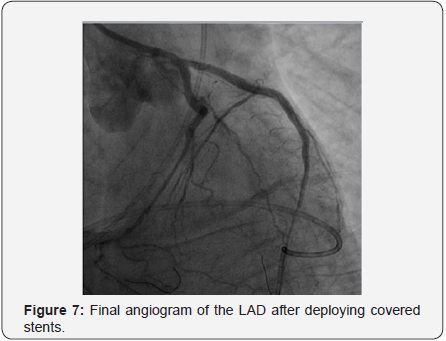

A 2.8x19mm polytetrafluoroethylene (PTFE) covered stent Graft-master stent (Abbott Vascular) was placed at mid to distal LAD at 16 atm followed by post-dilatation with 3.0x15mm Hiryu (TERUMO) HPB at 26 atm. Persistent dye extravasation was noted. Another 2.8x16mm Graft-master covered stent was placed at distal LAD overlapped the last one, sealing the perforation site as illustrated in Figure 7. The patient gradually improved under ventilator & IABP support.